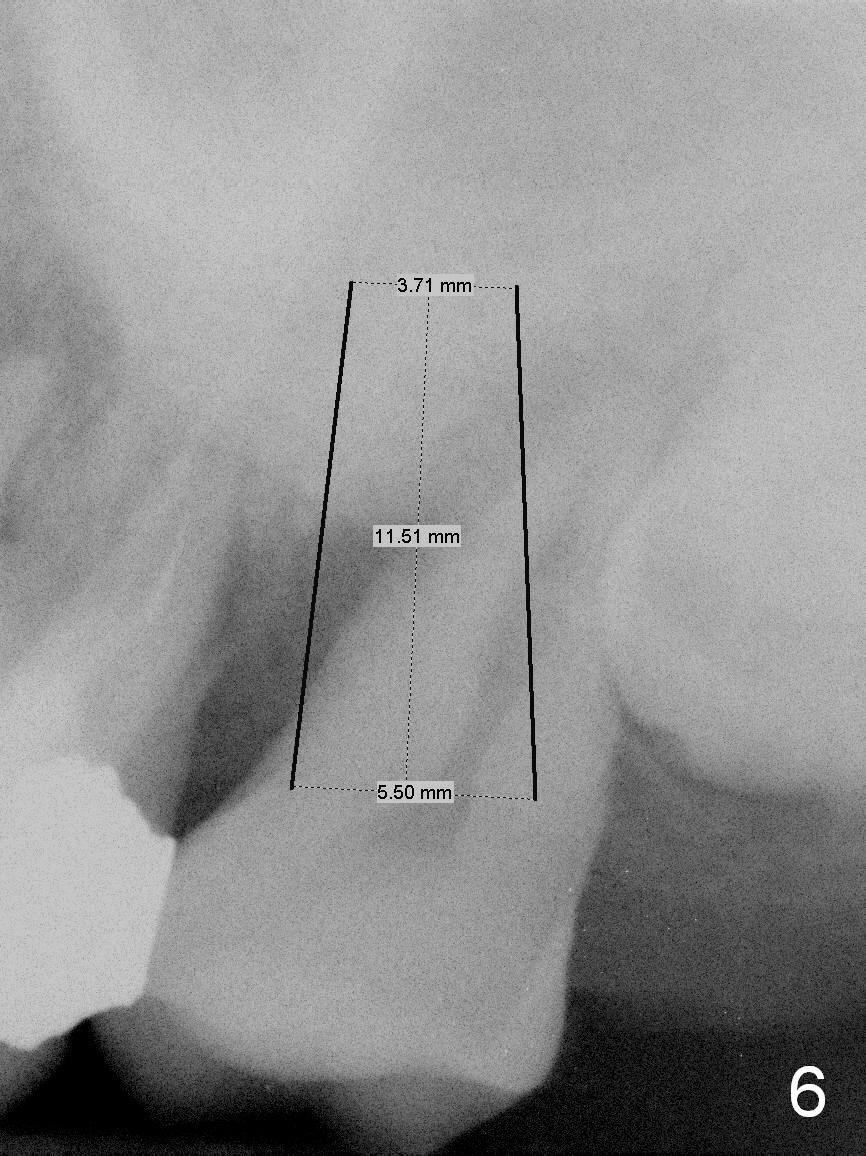

A 51-year-old lady (ZC) requests #15 extraction and immediate implant (Fig.1,2). The affected tooth is between periapical radiolucency of #14 (Fig.1 >) and the impacted 3rd molar (*). Discuss the possibility of extracting #14 and 16 at the same time. After extraction (Fig.3), osteotomy is initiated on the mesial slope of the socket (treated with Clindamycin, Fig.4). Once the cortex is penetrated, the trajectory is changed (Fig.5). After withdrawing the pilot drill, insert a parallel pin for X-ray. Adjust osteotomy position and angulation and finish placing an implant (Fig.6).